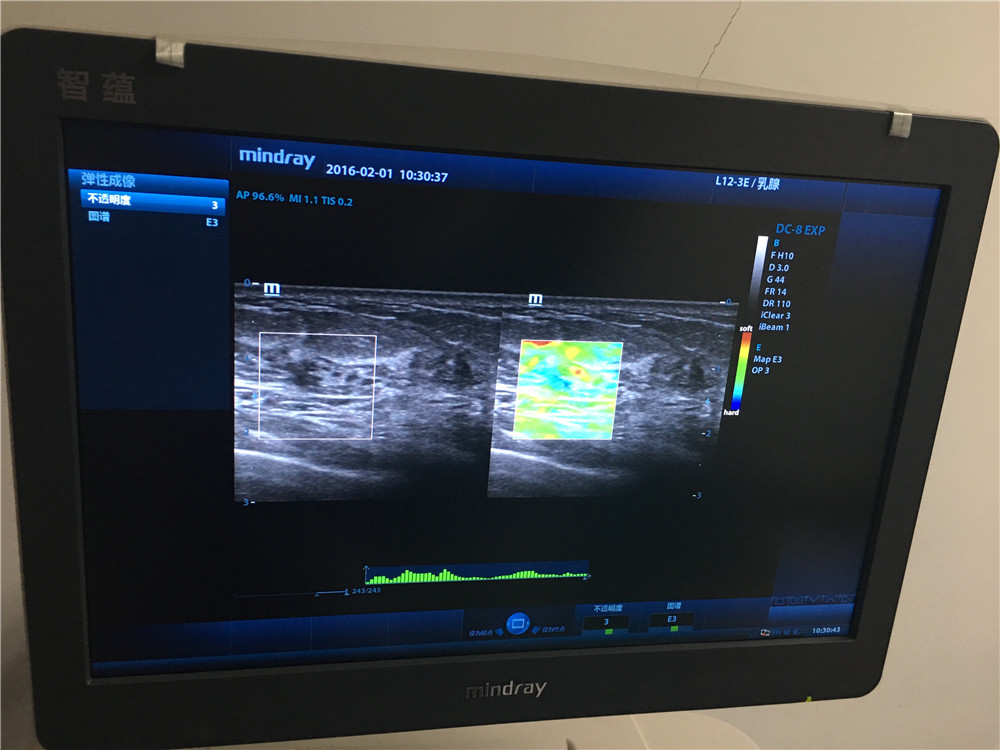

为进一步提高乳腺检查的敏感性和诊断的准确性,我院功能科在全市率先引进弹性成像这一辅助新技术,为早期诊断、鉴别乳腺肿瘤的良、恶性及早期治疗提供的一种新的有效途径。 作为一种全新的成像技术,弹性成像扩展了超声诊断理论的内涵和超声诊断范围,弥补了常规超声的不足,能更生动的显示、定位病变及鉴别病变性质,使现代超声技术更为完善。实时组织弹性成像不仅能帮助早期发现不易触及的微小及深在的病灶,在识别传统灰阶声像图上难以发现的病变浸润区域上也有优势,还能鉴别一些临床上较难诊断的乳腺病灶,如不典型的乳腺病及炎性病变。并且,如果弹性成像图与灰阶声像图上肿瘤的大小比较确可作为一种可靠的检测指标,那么临床早期发现恶性乳腺癌的比率将大大提高,需要接受活检以确定良恶性的患者数也将大大减少,既可帮助减轻社会医疗保健的经济负担,也可减轻患者自身身体和心理上的痛苦。其在临床上的应用包括:1.癌症的早期诊断;2.病变的良性、恶性判断;3.癌变扩散区域的确定;4.治疗效果的确认。

组织弹性成像除了在乳腺疾病方面研究较为深入,技术成熟外,目前还应用于前列腺、甲状腺等小器官,可有效鉴别实质性肿瘤的良恶性,对于恶性病变诊断具有较高的特异性和敏感性。另外还应用于肝纤维化的诊断、局部心肌功能评价以及高强度聚焦超声与射频消融引起的损害的检测与评估。